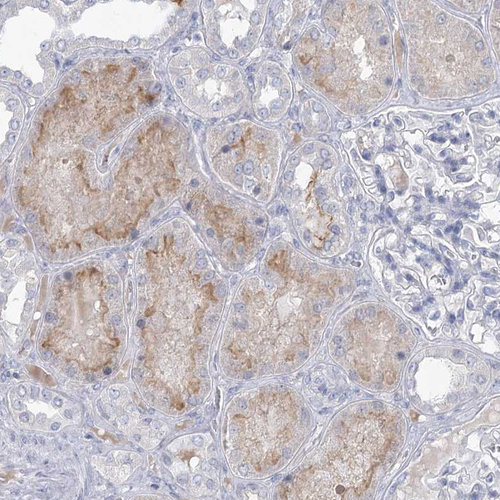

Immunohistochemistry analysis in human colon and liver tissues using HPA036669 antibody. Corresponding SLC9A3 RNA-seq data are presented for the same tissues.